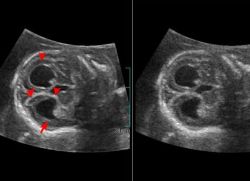

Диагностика на плода вентрикуломегалия

За разлика хидроцефалия фетален мозък вентрикули вентрикуломегалия разшири, когато по-голяма от 10 mm и по-малко от 15 mm, размер на плода главата не се увеличава. Вентрикуломегалия диагностицира чрез ехография от 17 седмици. Това може да се изолира асиметрична (единичен разширяване вентрикуларна или една от неговите рога) симетричен изолиран без други дефекти, или в комбинация с други малформации на мозъка и други органи. Когато изолира свързани вентрикуломегалия хромозомни аномалии, като например синдром на Даун, намерено в 15 - 20%.

Диагностициране вентрикуломегалия извършва на 17-33 седмица от бременността с помощта на ултразвук, спектрален кариотипиране плода. В изследването са включени пълен изследване на анатомичните структури на плода, особено по отношение на камерна система на мозъка.

А по-точно решение на диагнозата, поставена въз основа на сканиращата глава с плода задължителен праг определяне антропо. Заболяването се среща в случай че вентрикуларна размер е по-голям от 10 mm.

Вентрикуломегалия плода може да се диагностицира по време на бременността (17 до 33 седмици) с ултразвук и спектрален кариотипиране.

За да се установи точната диагноза прави напречен сканира главата на детето с определяне на антропо на мозъка. Когато им размер по-голям от 10 мм се диагностицират вентрикуломегалия. Размерът на мозъчните стомахчета на вентрикуломегалия може да достигне до 12-20 мм.